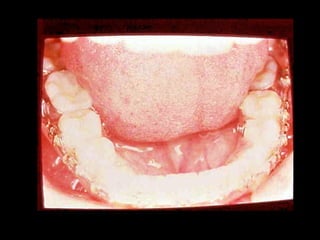

24 horas de postoperatorio

Maxilar:

Retenedor de Howley, sin interferencias oclusales.

Mandíbula:

Retenedor fijo de canino a canino